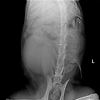

후두골이형성 질문드립니다 작성자 한수 작성시간 16.02.01 조회수 149